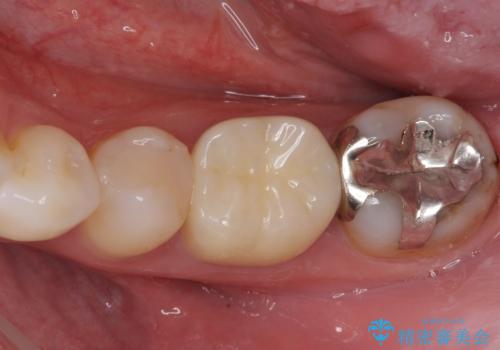

上顎は、元々の詰め物が小さく、欠けた範囲も大きくなかったため、セラミックインレーにて修復治療を行うこととしました。

一方下顎は、元々のむし歯の範囲が広かったため、長期的な予後を踏まえ、セラミッククラウンにて補綴治療を行うこととしました。

特に痛みはありませんでしたが、未然にしっかりとした処置を行うことで、今後むし歯の進行により神経組織が壊死するリスクを低減することが可能となります。